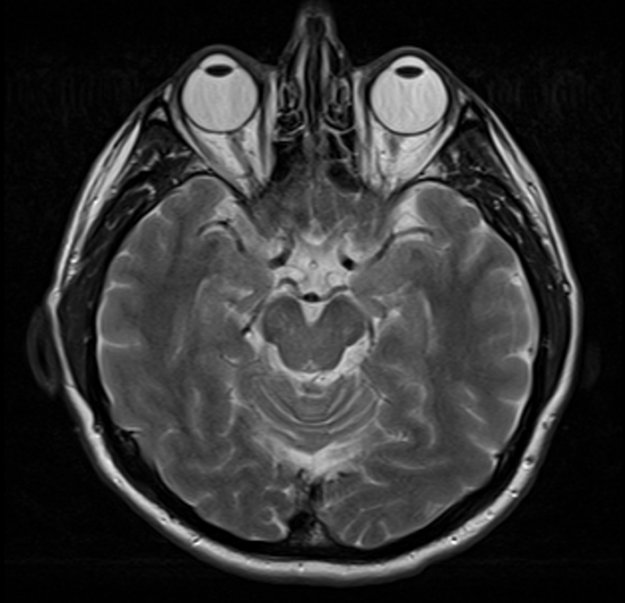

Badania naukowców z Mayo Clinic pokazały, że oprogramowanie do rozpoznawania twarzy może zidentyfikować człowieka wyłącznie na podstawie obrazu rezonansu magnetycznego.

Naukowcy odkryli, że na podstawie istniejącego już teraz oprogramowania do identyfikacji twarzy są w stanie w 83% przypadków dopasować pacjenta do jego obrazu MRI (rezonans magnetyczny). Badanie MRI pozwala m.in. na określenie stanu mózgu oraz rdzenia kręgowego. Pozwala też wykryć tętniaki oraz rozwój udaru.

Eliot Siegel, profesor radiologii z Mayo Clinic, twierdzi jednak, że zagrożenie wbrew pozorom nie jest duże. Oprogramowanie było w stanie z 83% skutecznością powiązać człowieka z jego rezonansem magnetycznym przy grupie badawczej złożonej z 84 pacjentów. W praktyce jest ich dużo więcej, co powinno wydłużyć znacząco czas operacji i zmniejszyć jej skuteczność.